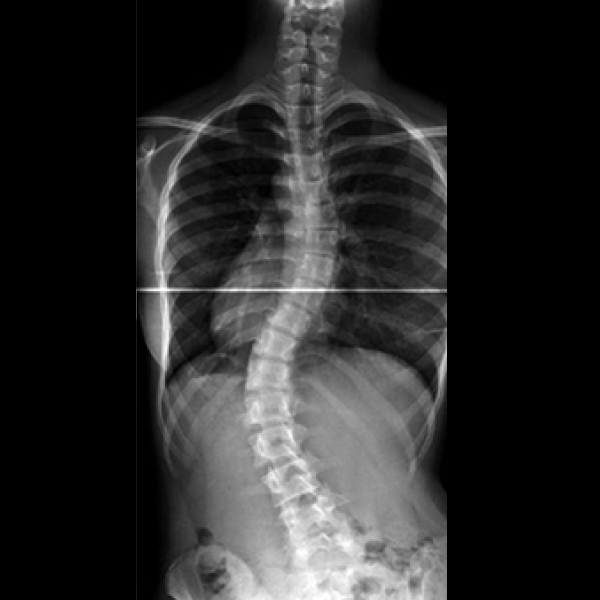

척추측만증 진단 질병후유장해 보상여부

오늘은 경추측만증으로 질병후유장해(3~80%)

보상 가능한지에 질문사항

경추측만증도 질병후유장해 포함이 되나요?

후유장해지급률 15~30%의 장해율이

인정 될 수 있습니다.